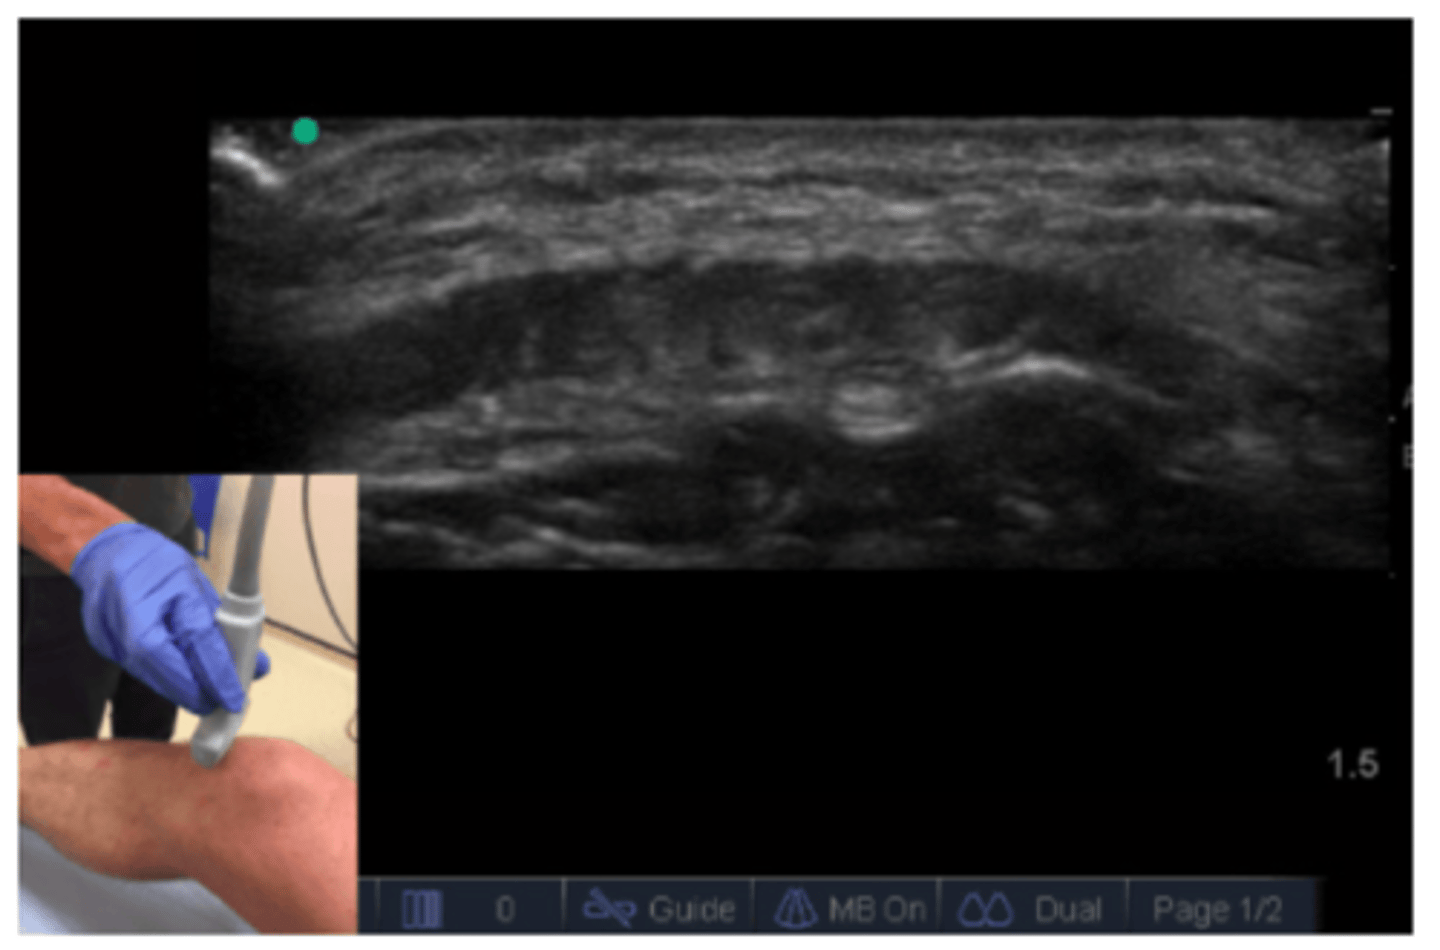

___________: probe orientation that allows for a longitudinal/vertical/up & down scan

Long axis

___________: probe orientation that allows for a transverse/horizontal/left & right scan

Short axis

What would a transverse vs. longitudinal ultrasound of the shoulder look like?

See image.